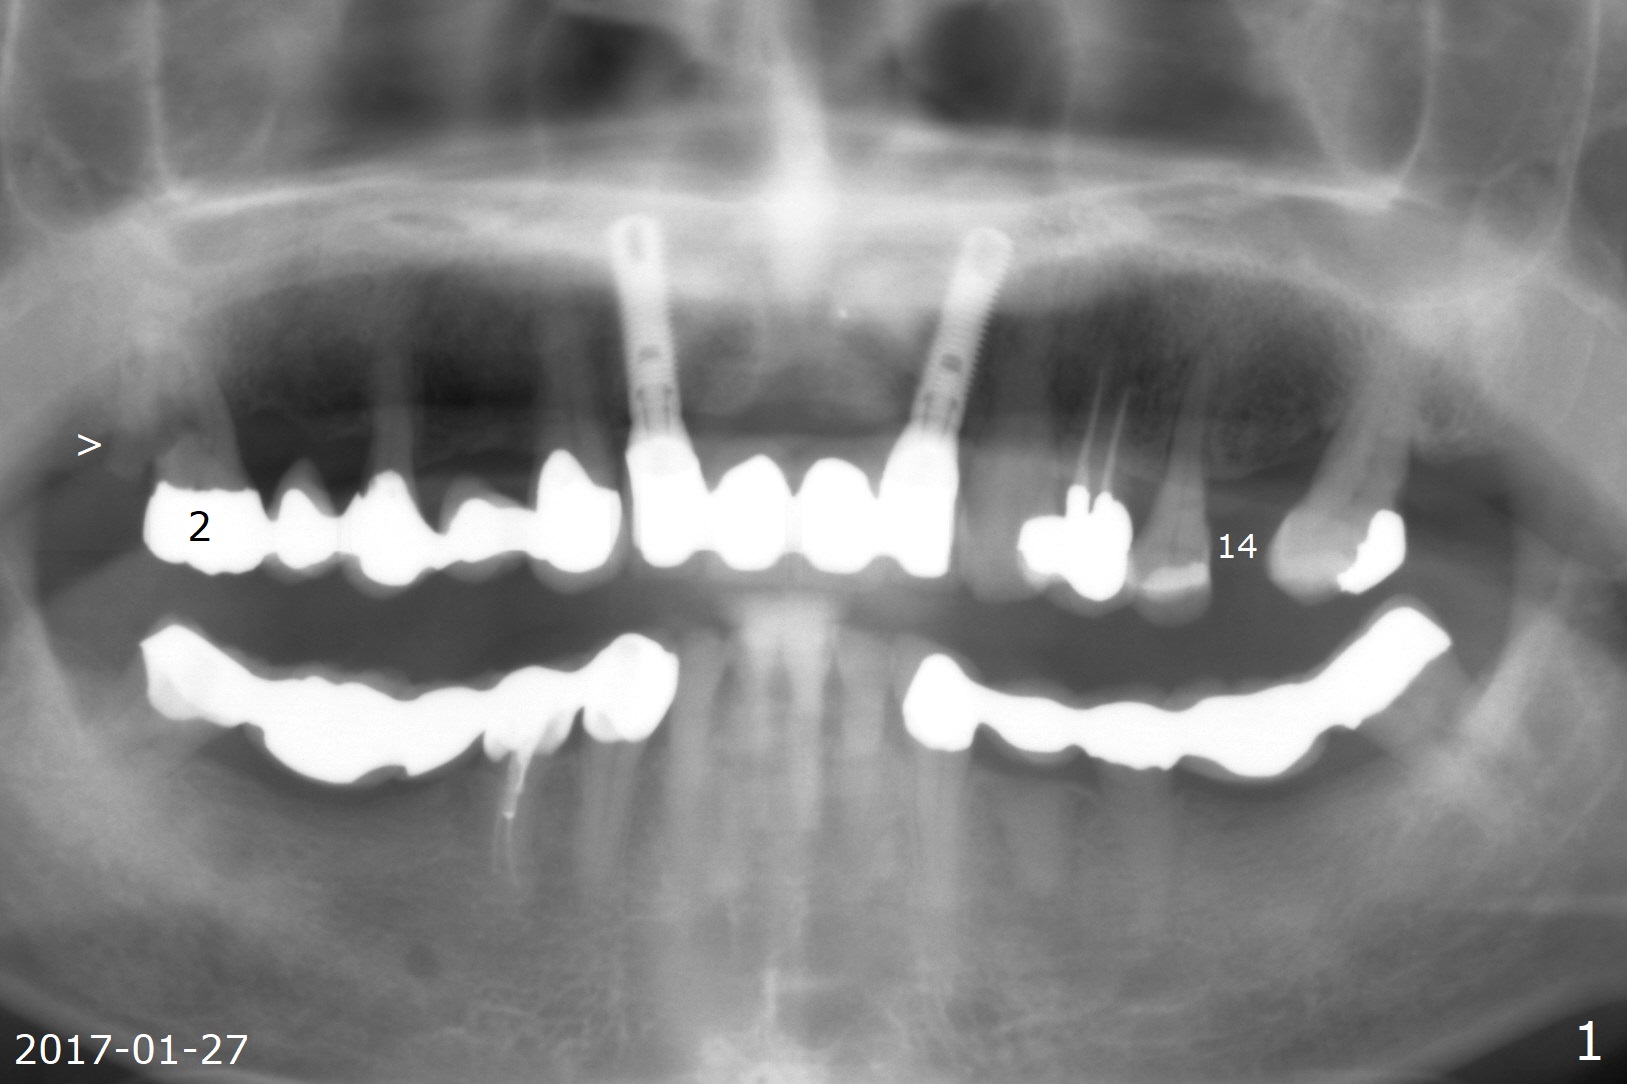

A 66-year-old man has asymptomatic distobuccal (DB) root fracture for ~ 3 years (Fig.1 (>) 2). After #14 implant with limited (M) ortho and 27 and 31 RCT (Fig.3,4), he agrees to have #2 and 3 implants. The tooth #2 has palatal fistula and is tender. Take preop photos. CT should reveal extensive bone loss. Use PRF/sticky bone or GEM21S (if venopuncture is hard) for repair. Save bone from #3 osteotomy for #2 bone graft. Use a special suction with trap after granulation tissue removal.